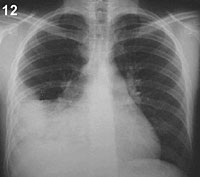

ESQUEMA 12 Comentario placa 12 Cuando las condensaciones contactan con otras estructuras densas como el corazón y el diafragma, el contorno de estas últimas se borra por falta del contraste entre sólido y aire Se observa una condensación situada en la base pulmonar derecha en un área que puede corresponder tanto al lóbulo medio como al inferior derecho y sería necesaria una placa lateral para identificar el lóbulo comprometido. Sin embargo, el borramiento completo de la parte baja del borde derecho de la silueta cardíaca indica que la condensación está en contacto con el corazón cuyo borde no se percibe por no contrastar con el parénquima que está condensado (signo de la silueta). Esto significa que está afectado el lóbulo medio. Además, la condensación tiene como límite superior la cisura horizontal (H). El diafragma se alcanza a ver con dificultad. Ponga la placa 13 que muestra una condensación situada en el pulmón izquierdo y anote como está el borde cardíaco. Atras | Indice | Siguiente |